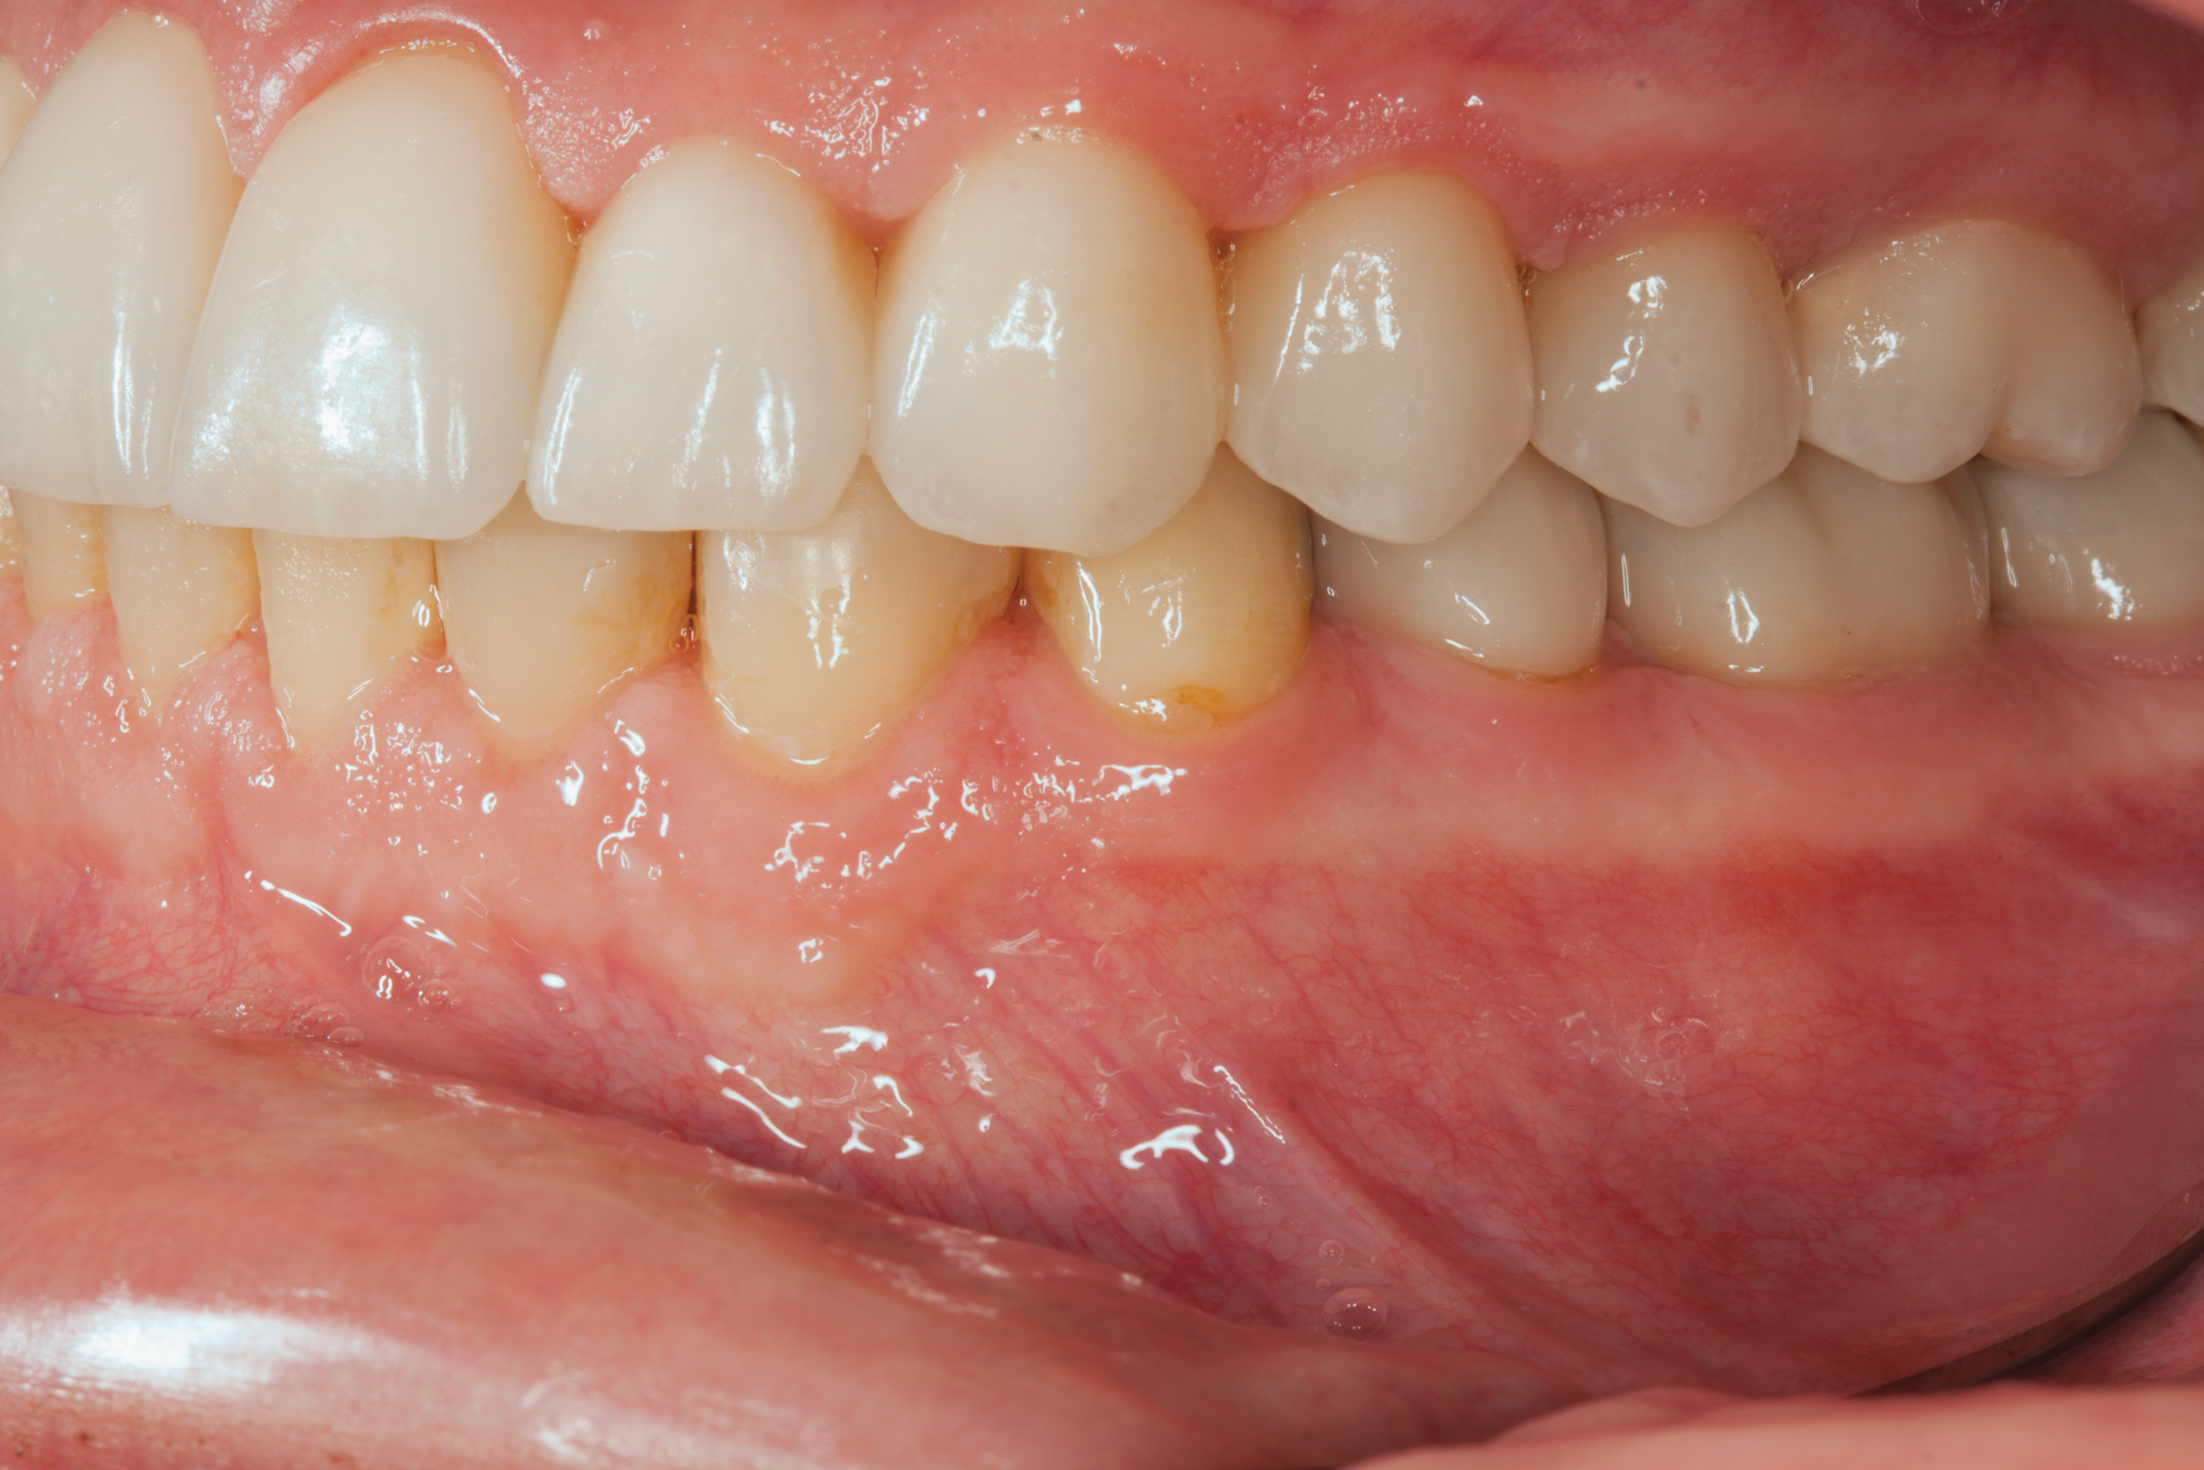

Fig 4. Left lateral view of patient with worn dentition. Note loss of vertical dimension in posterior as evidenced by the buccal cusp tip position of tooth No. 12 versus the papillary tissue of teeth Nos. 20 and 21.

Figure 4

Fig 14.  Prosthetic phase completion. Left lateral view. Note vertical dimension change in posterior as evidenced by the buccal cusp tip position of tooth No. 12 versus papillary tissue of teeth Nos. 20 and 21 as compared to initial presentation (Fig 4).

Figure 14